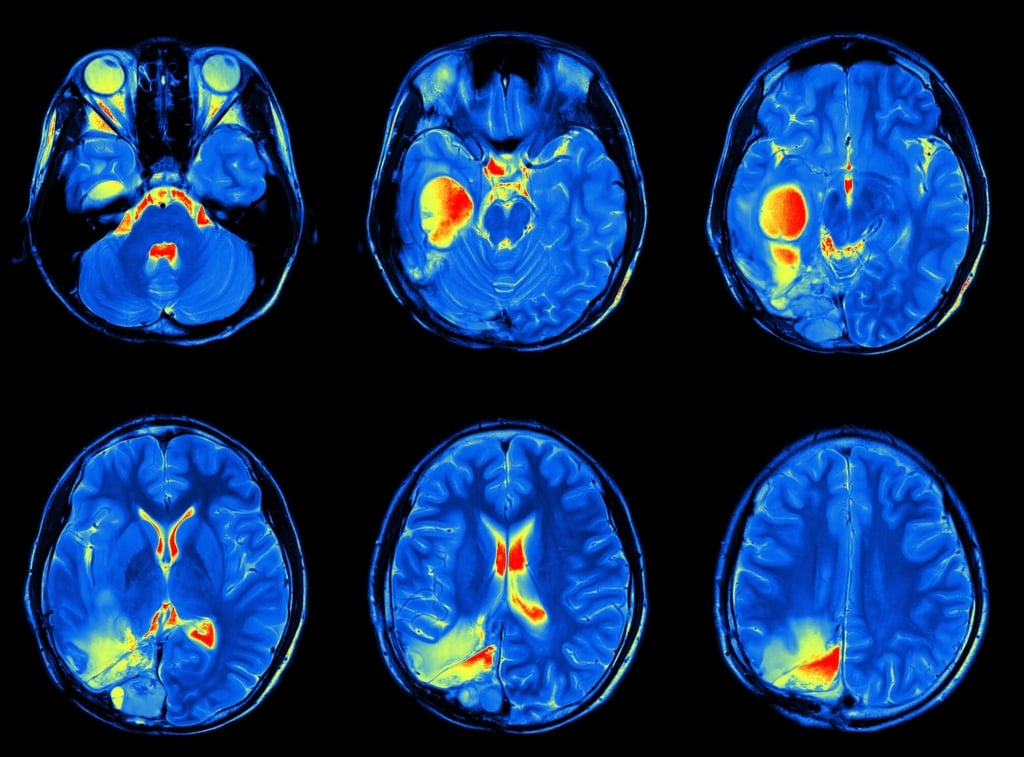

L’autismo è un disturbo che insorge in età infantile. Caratteristiche principali sono il deficit sociale, di comunicazione interpersonale e la presenza di movimenti ripetitivi e senza finalità. Una sorta di isolamento nel quali i piccoli sembrano essere incapsulati e distaccati dalla realtà. Nei disturbi dello spettro autistico ad essere alterata è la comunicazione tra le diverse aree cerebrali. Assottigliamento delle fasce nervose che connettono le zone tra loro e difetti nelle sinapsi tra neuroni sono solo alcuni dei danni strutturali rilevati. Purtroppo, prima dei due anni, fare diagnosi è molto difficile perché l’autismo non da sintomi. Eppure, come dimostrato nello studio degli scienziati americani, le tracce del disturbo potrebbero essere già presenti nei primi mesi di vita.

Per arrivare a questa conclusione gli autori hanno analizzato il cervello di 106 bambini - con in famiglia un fratello o sorella autistico - tramite risonanza magnetica all’età di 6, 12 e 24 mesi. Analizzando le immagini gli scienziati hanno scoperto a posteriori che il cervello dei bambini con autismo (a 25 dei 106 partecipanti è stato diagnosticato dopo i 2 anni) presentava un ritmo di crescita maggiore rispetto ai non autistici nel periodo compreso tra i 12 e i 24 mesi di età. Non solo, il dato più interessante riguarda quanto scoperto nei primi 6 mesi di vita. Dalle immagini delle strutture cerebrali emerge infatti che la superficie della corteccia cerebrale cresce più in fretta.